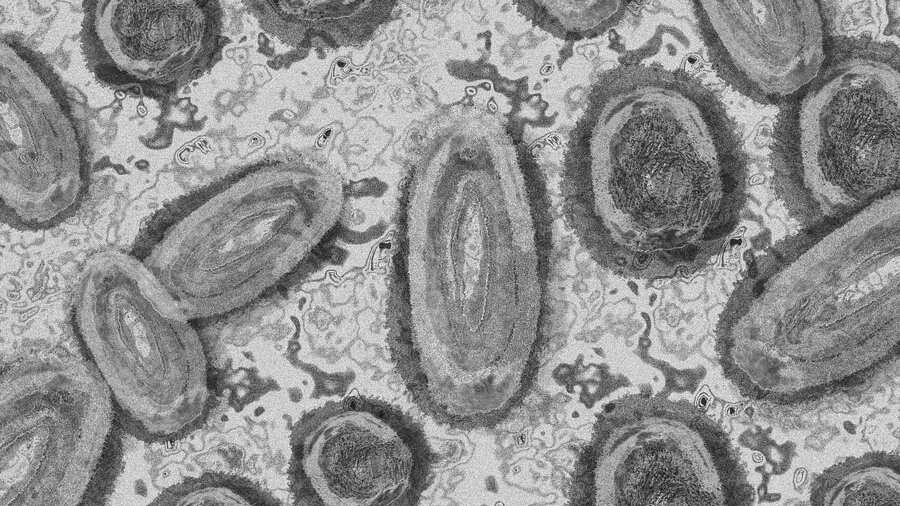

El Ministerio de Salud Pública y Asistencia Social (MSPAS) emitió una circular con fecha del 24 de mayo de 2022 para informar a los hospitales públicos y privados sobre el procedimiento de manejo y notificación de casos sospechosos de Viruela Símica o también conocida como Viruela del Mono.

“Es una enfermedad infectocontagiosa que produce síntomas parecidos a los que se observaban en los pacientes diagnosticados con la viruela conocida en el pasado, aunque estos se presentan de forma menos grave”, indica la misiva.